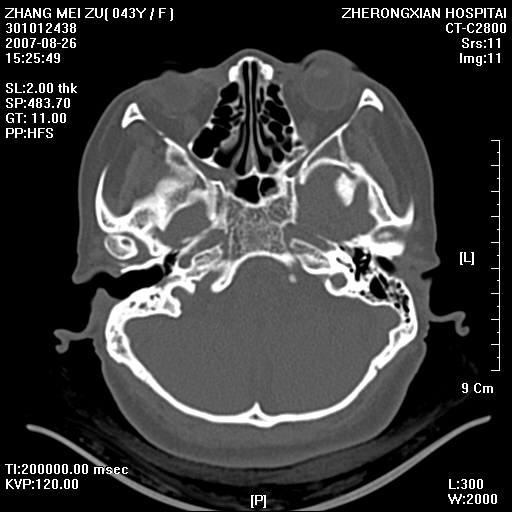

标题: CT9512:F43Y,是肉芽肿还是胆脂瘤?诊断报告该如何出? [打印本页]

标题: CT9512:F43Y,是肉芽肿还是胆脂瘤?诊断报告该如何出?

右耳硬化性乳突炎并胆脂瘤形成

右耳硬化性乳突炎并鼓窦入口胆脂瘤形成,左侧乳突炎

右侧中耳乳突炎,伴鼓窦入口胆脂瘤形成.

从发病部位及骨质破坏应该考虑是获得性胆脂瘤

典型胆脂瘤,从上鼓室,乳突窦入口到乳突窦有明显光滑的骨质破坏和软组织结节均为胆脂瘤特点.而肉芽肿对骨质的破坏是轻微的.值得关注的是乳突后壁被破坏只剩薄薄的一层,如果再不尽快治疗,胆脂瘤如果突破其后壁即可能形成耳源性脑脓肿了.